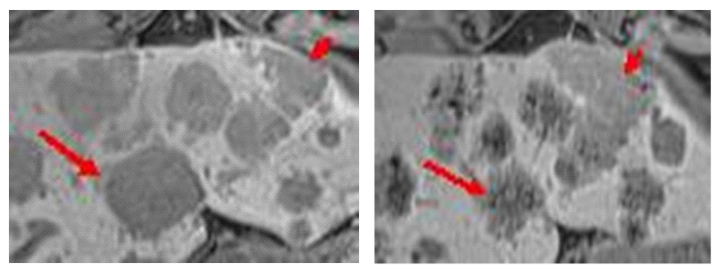

Figure 2a and b shows a liver metastasis (short arrow) in the left lobe without significant signal change by Inlyta® therapy. It has come in the recording control to a size increase (PD, Recist 1.1). The metastasis (long Arrow) with a decreased signal becomes progressively smaller (PR, Recist 1.1). The correlation between signal quality and size in the adjacent liver metastases in the same patient may reflect the different biology or vascularization of the cell assembly. Standard independent image review for oncology study (RECIST) includes only the criterion of the size of the lesion. Maybe the criterion of signal reduction is an additional useful indicator for treatment response or not-response.

Figure 2MRI, TIM Trio, 3 Tesla (SIEMENS), Gradient Echo T1-weighted, transversal, 10 ml Primovist®, storage phase. Enlarged section from a single sectional image of untreated liver metastasis (left) and treated liver metastasis (right). The therapy with Inlyta® generates a strongly hypointense, mulberry-like signal in the metastases. These metastases are reduced in size (long arrow). Other metastases show only occasional point-like signal attenuation after therapy. These are rather increasing in size (short arrow).